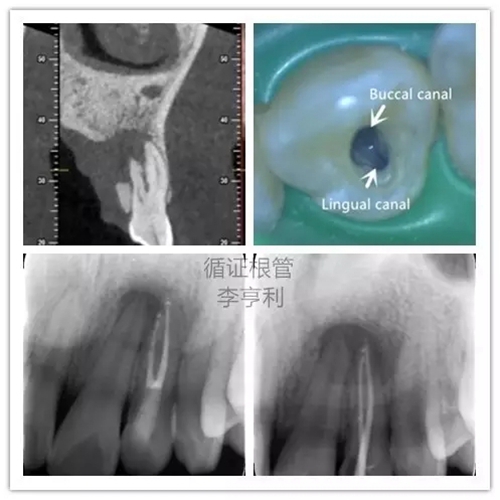

5,根管解剖的評估

上頜側(cè)切牙擁有雙根管

在CBCT的掃描中,根管形態(tài)能在三維的條件下評估,能準確顯示根管數(shù)量和多個根管之間的聯(lián)系。根據(jù)Matherne et al. (2008)的間接體外研究(ex vivo),牙體牙髓??漆t(yī)生單憑閱讀數(shù)碼X片,即使一個牙齒進行多個角度拍攝,還是有40%的樣本牙齒出現(xiàn)至少一個遺漏根管。

對于最容易被疏忽的上頜磨牙MB2根管,CBCT正確判斷其是否存在的幾率高達79%,與金標準的牙齒切片(sectioning)準確率無統(tǒng)計學(xué)上的區(qū)別(Blattner et al. 2010)。所以,即使對于非手術(shù)性的根管再治療(non-surgical retreatment),CBCT也能提供巨大的治療價值。